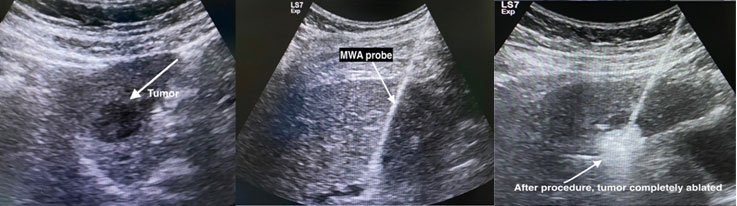

Radiofrequency ablation (RFA) and microwave ablation (MWA) are treatments that use image guidance to place a needle through the skin into a liver tumor.

In MWA, microwaves are created from the needle to create a small region of heat. The heat destroys the liver cancer cells.

RFA and MWA are effective treatment options for patients who might have difficulty with surgery or those whose tumors are less than 5cm in diameter.

The success rate for completely eliminating small liver tumors is greater than 85 percent.

MWA procedure for HCC